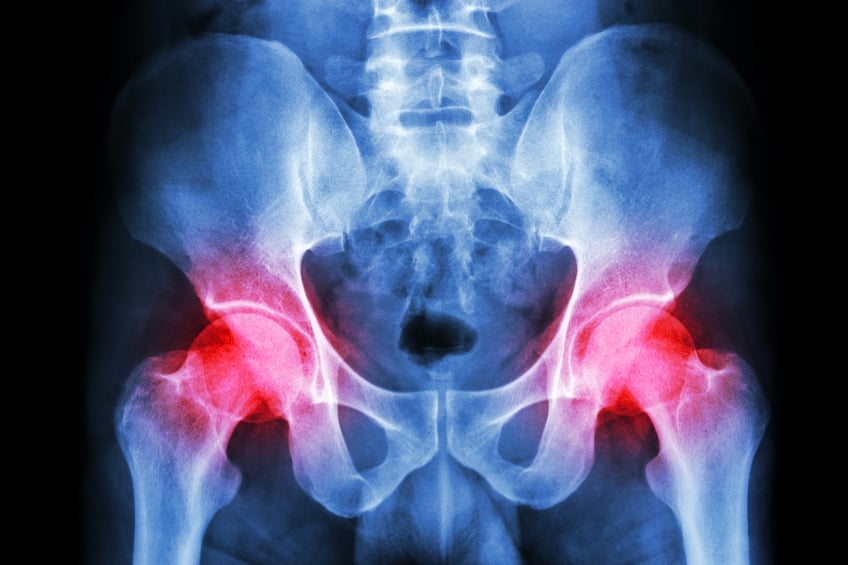

Le fémur forme, avec le bassin, l’articulation de la hanche qui permet notamment de marcher. La tête arrondie de la partie haute du fémur s’emboîte à la perfection dans le cotyle, le creux de la hanche. Pour un sujet jeune, ces zones sont recouvertes de cartilage qui permet un mouvement fluide. En revanche, chez une personne âgée, ces cartilages peuvent être endommagés par l’ostéoporose, ce qui rend la zone fragile. La moindre chute peut alors entraîner une fracture du col fémoral ou du massif des trochanters. Une prise en charge d’urgence est nécessaire.